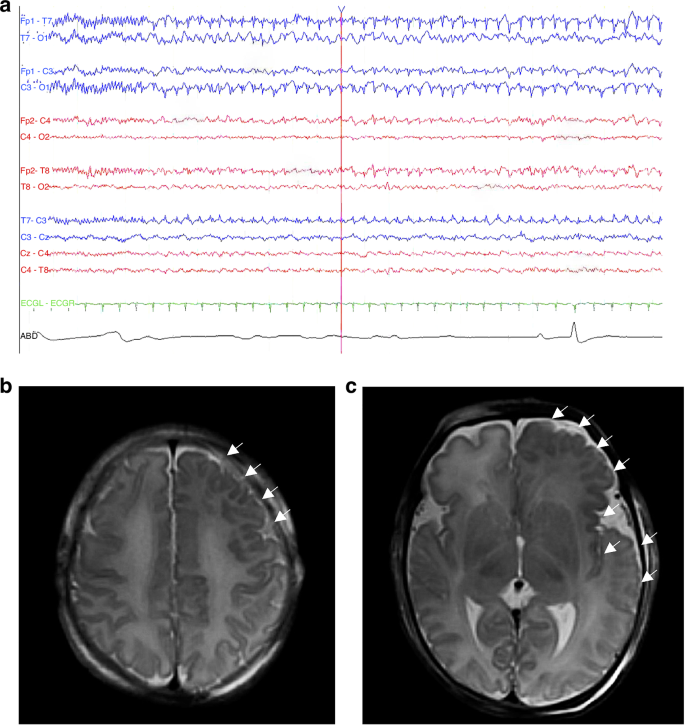

Neonatal encephalopathy in the population with congenital neurological disorders merits discussion because it can co-exist due to seizures, metabolic disorders or disturbances, or unrelated diagnoses like sepsis.47 Hypoxic-ischemic encephalopathy (HIE) has been documented in neonates with congenital neuromuscular disorders and brain malformations in observational cohort studies and clinical trials.48,49,50,51,52 For example, an early case series of congenital myotonic dystrophy reported that 13/14 neonates had evidence of perinatal HIE with poor fetal to neonatal transition.48 The diagnosis of neonatal encephalopathy may precede the diagnosis of a congenital neurological disorder, which may be identified on brain MRI after rewarming from therapeutic hypothermia (Fig. 1) or based on neurological examination findings that are not explained by the infant’s clinical course, EEG, or MRI.49,50,51 A case series of term neonates with encephalopathy that underwent therapeutic hypothermia for suspected HIE reported 8/137 (6%) cases treated over the study period were subsequently diagnosed with a congenital anomaly or genetic disorder.49 In the Phase 2 trial of erythropoietin plus therapeutic hypothermia for perinatal HIE,50 2/50 (4%) participants were diagnosed with another neurological disorder after completing hypothermia. In the randomized Phase 3 HEAL trial of erythropoietin plus therapeutic hypothermia for perinatal HIE,52 24/500 (5%) were found to have a congenital anomaly or genetic disorder, of which there was a wide range of conditions with no apparent linkage to HIE.51 There have been no safety concerns in the cases of brain malformations and genetic disorders treated with therapeutic hypothermia for HIE reported in the literature, and it is possible for two conditions to co-occur. HIE in addition to an underlying congenital anomaly or genetic disorder may also further impact neurodevelopmental outcome depending on whether there is resulting acute perinatal injury. The brain malformation or genetic disorder may also increase risk for HIE, so it is important to consider this when evaluating patients with neonatal encephalopathy.

a Electroencephalography on day 3 showing seizure arising from the left frontal region with spread to the left hemisphere. b, c Axial T2-weighted MRI after rewarming showing asymmetric enlargement of the left hemisphere with frontotemporal polymicrogyria (white arrows) and hyperintense white matter. Whole exome sequencing was negative; however, genetic testing on resected tissue following hemispherotomy showed a variant in MTOR. Routine prenatal anatomy ultrasound was normal in this case, and fetal brain MRI was not obtained.